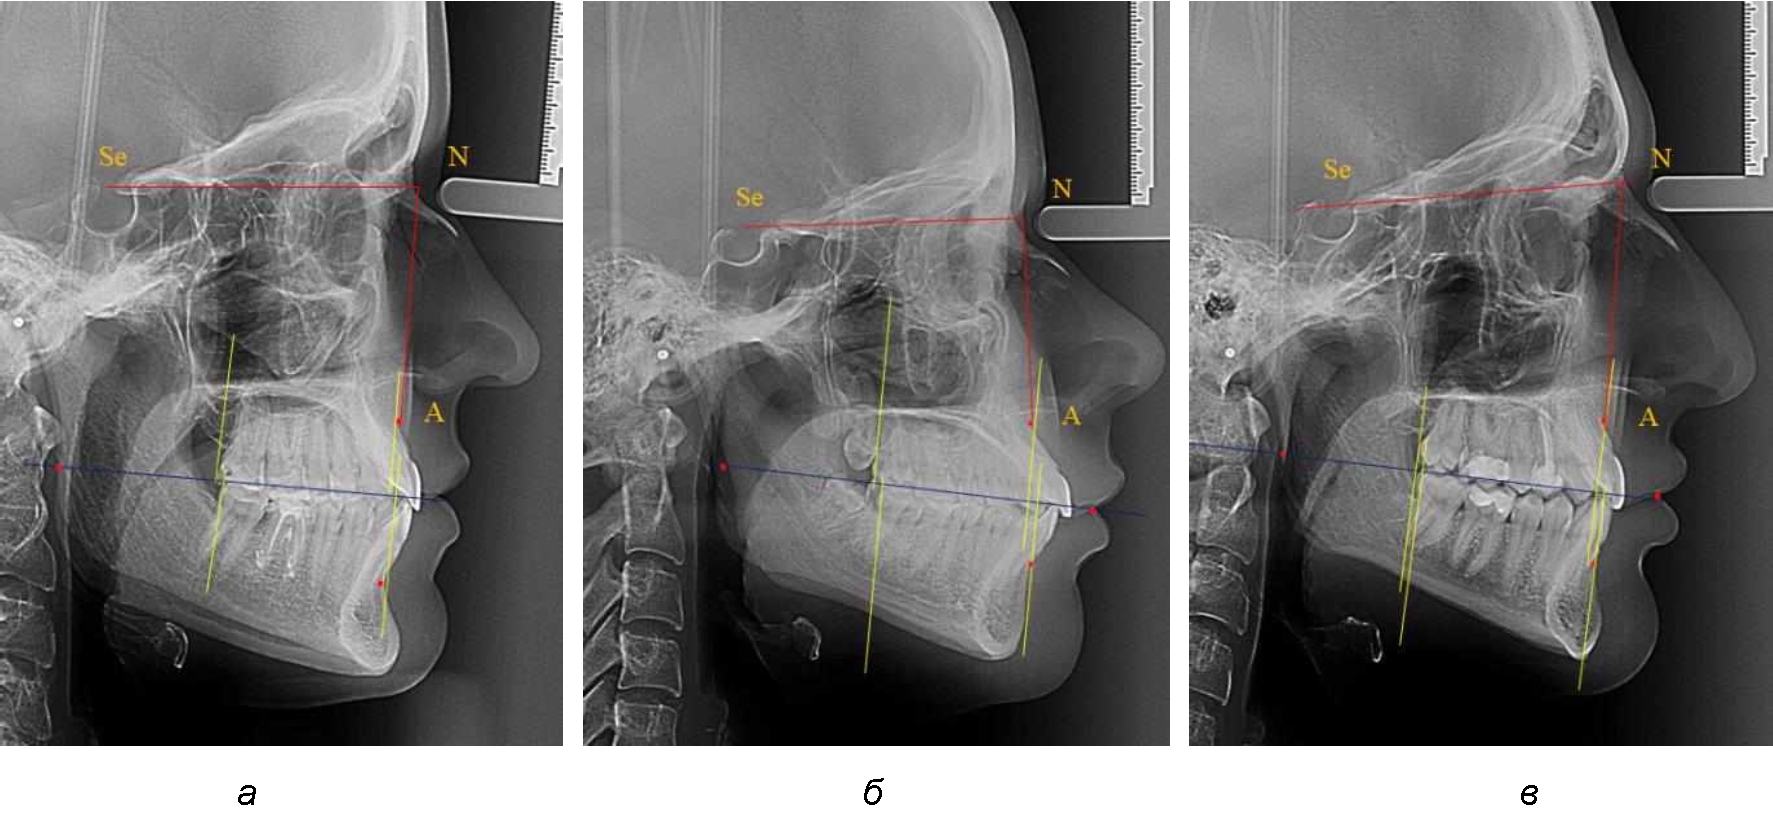

На рентгенограммах устанавливали точки Downs. На верхней челюсти субспинальная точка A(SS) располагалась в наиболее вогнутой точке альвеолярного отростка по переднему его краю. На нижней челюсти супраментальная точка B(SM) соответствовала месту наибольшей вогнутости переднего края альвеолярной части. Окклюзионную линию проводили через контактную точку резцов (vРOcP) и дистальную точку окклюзии второго нижнего моляра (hРOcP). Место пересечения окклюзионной линии с дистальным краем ветви нижней челюсти (ramus mandibule) обозначали как «rmРOcP». Перпендикулярно к окклюзионной плоскости проводили линии из точек «А(SS)» и «В(SМ)», что определяло их проекцию на окклюзионную линию. Аналогично отмечали положения дистальных окклюзионных точек верхней и нижней челюсти (рис. 1).

Рис. 1. Положение основных точек (а) и линейных ориентиров (б) для анализа положения и размеров челюстей

Альвеолярно-дентальный размер верхней челюсти и нижней челюсти оценивали по окклюзионной линии между вертикалями, ограничивающими исследуемые челюсти. Положение верхней челюсти оценивали по величине размера «rmOcP-А», а нижней челюсти по расстоянию «rmOcP-В». Линия смыкания губ обозначалась как точка «sto», вблизи которой проходила окклюзионная линия. Данный ориентир позволял провести окклюзионную плоскость при аномалиях положения резцов в вертикальном направлении, когда была сложность определения резцовой окклюзионной точки (vРOcP).